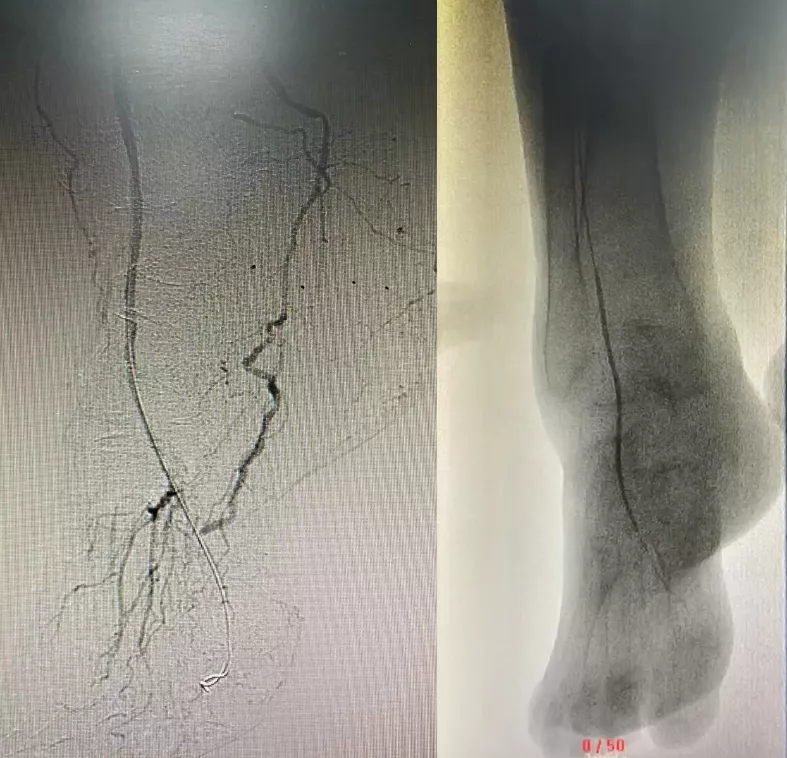

微创介入手术,是指用特殊的穿刺针穿刺动脉,从这个穿刺眼放入一些特殊的导丝和导管,在X线的监视下,到达病变血管,用球囊扩张狭窄动脉,然后用特制的金属支架支撑狭窄部位从而达到扩大下肢动脉管腔、恢复肢体血流的治疗目的。

以开头的阿婆为例,就是通过微创介入手术,用导丝开通她的足背血管,直通脚趾,恢复了阿婆的下肢血供。

图示:术前,股浅动脉长段闭塞,局部可见侧支循环

图示:术后,开通股浅动脉,血流通畅